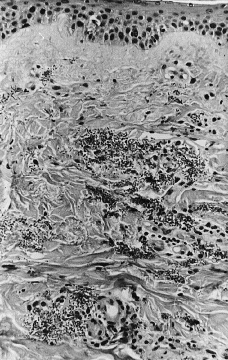

En la exploración física se observaron máculas purpúricas y pápulas con el centro hemorrágico y necrótico en cara (Fig. 1), antebrazos y piernas (Fig. 2) y úlceras necróticas en maléolo externo derecho y labio superior. Las lesiones eran escasas y asintomáticas.

FIG. 2.--Pápula necrótica en pierna derecha.

Se realizó biopsia cutánea para estudio histopatológico y cultivo. En 48 horas se recibieron los cultivos en sangre y piel con crecimiento de Trichosporon asahii, por lo que se añadió fluconazol al tratamiento. La paciente quedo afebril, pero se mantuvo la pancitopenia, con disnea y anuria, falleciendo 5 días después. El estudio histológico confirmó el tromboembolismo micótico que ocupaba la luz y pared vascular, que con la tinción de PAS ponía de manifiesto numerosas hifas y conidias (Figs. 3 y 4).

FIG. 4.--Hifas en luz vascular y zona extravascular. (PAS, ×400.)